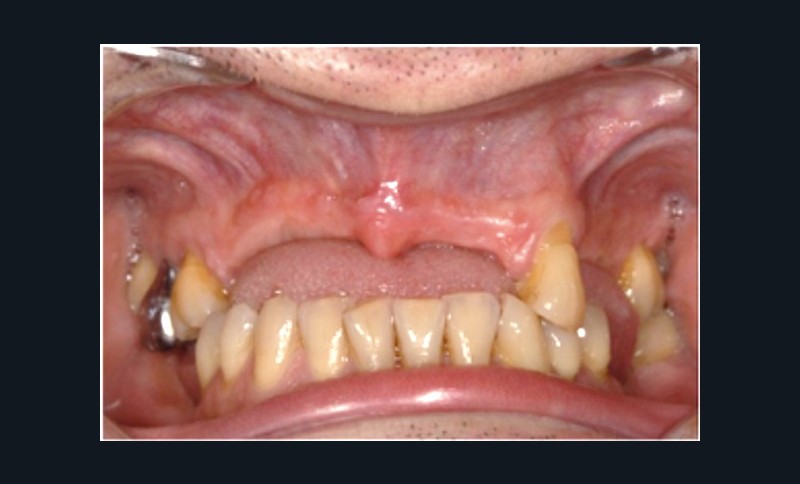

Cette partie de la présentation ne se contentait pas de rapporter les principes précédemment décrits à des régions limitées des maxillaires mais étendait la discussion à la difficulté majeure rencontrée en implantologie : rattraper des erreurs de positionnement implantaire ayant entraîné des compromis prothétiques inesthétiques. La solution thérapeutique mise en œuvre par Benoît Philippe consiste à appliquer la procédure d’ostéotomie segmentaire à l’entité constituée par l’os alvéolaire péri-implantaire et les implants. Les couronnes implantaires sont déposées. Le tracé d’ostéotomie encadre le segment à repositionner mais n’implique pas la corticale palatine qui sera fracturée pour éviter toute lésion du périoste (nourricier du segment alvéolo-implantaire). Un dispositif prothétique préparé en amont guide la translation du fragment qui est fixé au moyen de plaque d’ostéosynthèse dans la situation idéale. Le capital squelettique est reconstruit et l’espace prothétique disponible est normalisé.

Au cours de la conférence, Benoît Philippe a énoncé ses convictions concernant les conditions de succès du traitement implanto- prothétique : le respect d’une biomécanique implantaire équilibrée, le recours à des implants plus fins et moins nombreux que ne l’imposaient les préconisations d’autrefois, l’observation du biotype parodontal plus ou moins favorable aux reconstructions des atrophies étendues, la nécessité de restaurer au préalable puis de maintenir un environnement parodontal satisfaisant (en particulier la gencive attachée péri-implantaire).